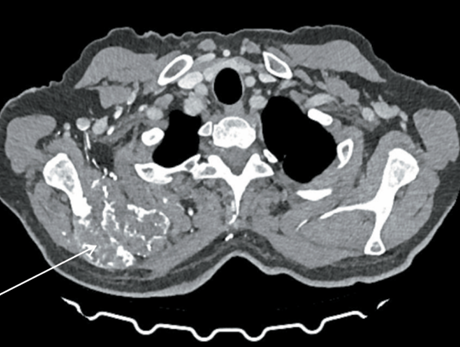

3. Рис. 3. МСКТ органов грудной полости (22.09.25): образование правой лопатки после 54 циклов поддерживающей терапии по схеме атезолизумаб + бевацизумаб. В ости и верхней трети тела правой лопатки сохраняется неоднородной структуры объемное образование с признаками «вздутия», с деструкцией костной ткани, с мягкотканым компонентом, распространяющееся в мягкие ткани, неравномерно накапли вающее контраст, размерами 69×53 мм, с наличием остео бластического компонента. Примечание: рисунок выполнен авторами